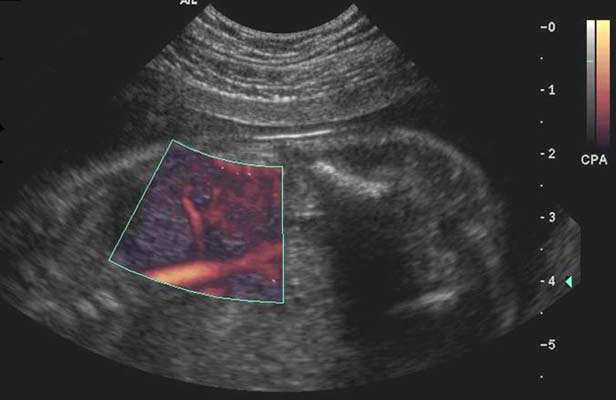

7 - Intérêt du Doppler couleur dans les pathologies de l'appareil urinaire

Visualisation de flux :

- vasculaire (angiographie)

- urinaires

Angiographie rénale :

- Le tronc de l’artère rénale est toujours vu, les segmentaires les sont souvent, les artères interlobulaires et arquées parfois.